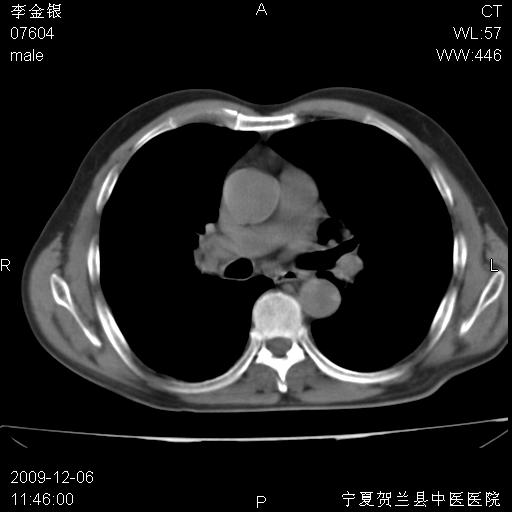

右上叶支气管狭窄,管壁增厚,远端斑片状软组织影,病灶邻近叶间裂,叶间裂无移位。

诊断右肺中央型肺癌。

那个片影应该大部分都是病灶,病灶沿肺段支气管分支生长,后段完全显示不清、闭塞。若为不张应该伴有叶裂的移位,若为炎症应有空气支气管征。

右肺中心型肺癌伴阻塞性肺炎及右肺门与纵膈淋巴结转移很典型,可纤维支气管镜进一步检查

考虑右侧中央型肺癌伴右肺上叶后段阻塞性炎症、肺不张、右肺门和纵隔淋巴结肿大。

右肺上叶中心型肺癌,阻塞性肺炎、右肺门和纵隔淋巴结转移。